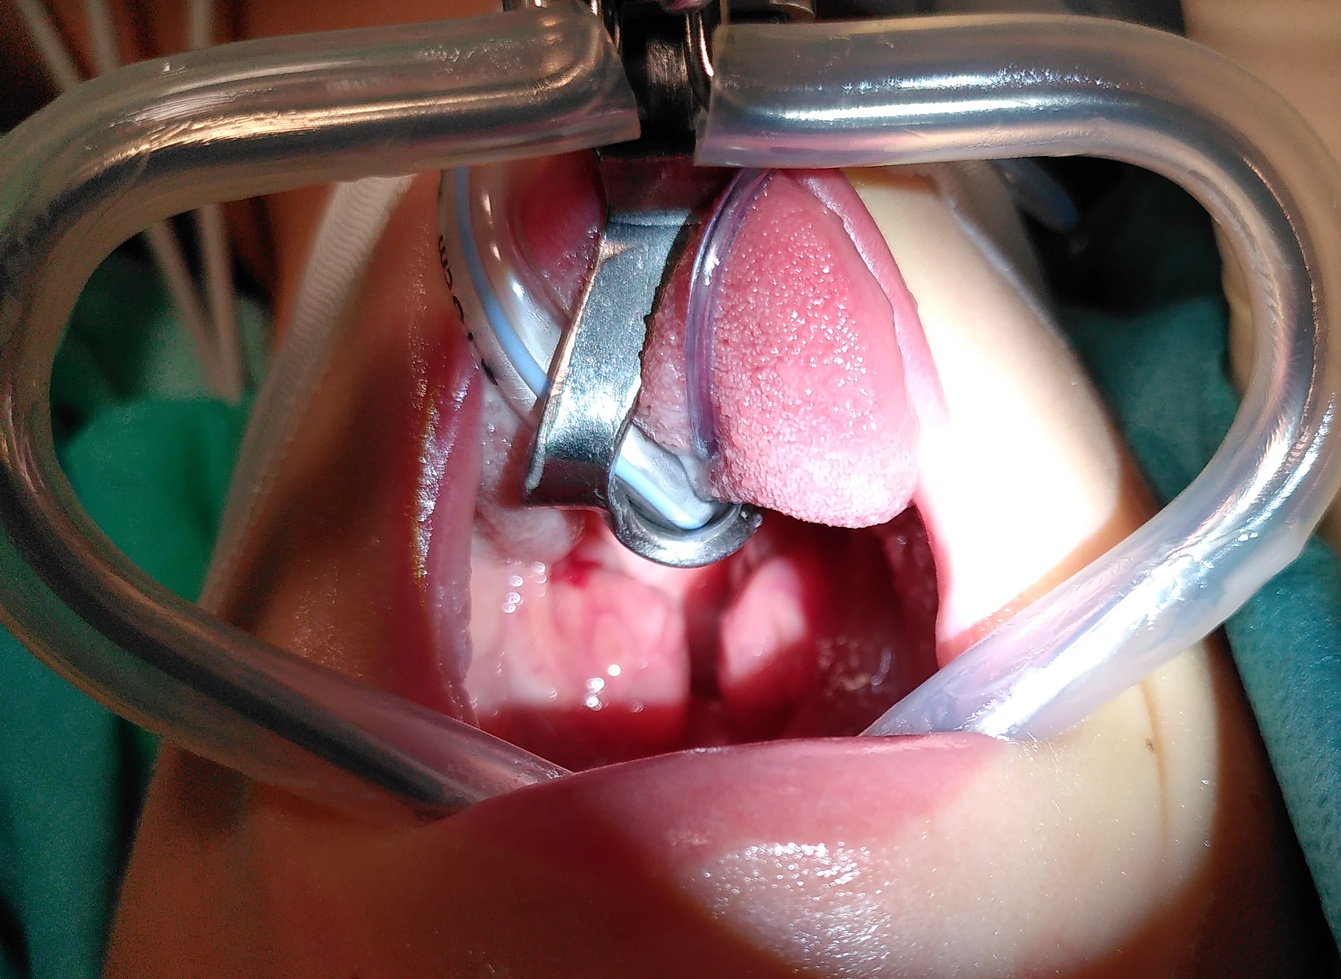

Beispiele herausfordernder Atemwege#

Tonsillenhypertrophie Tonsillenhypertrophie

Fig. 5 Bilderserie: Herausfordernde Atemwege 1#